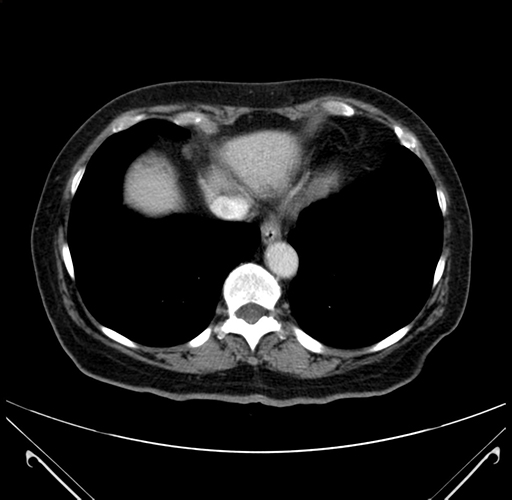

Pre-Chemo: Axial Venous